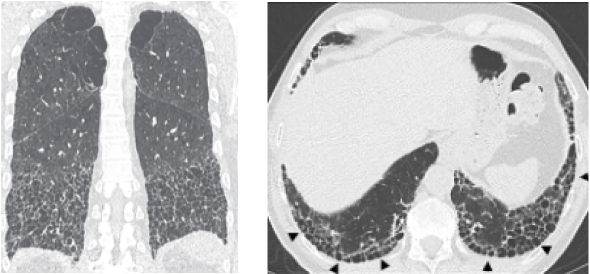

若發現異常則進一步以高解析電腦

斷層掃描檢查肺部切面 -

菜瓜布肺病人的 HRCT 檢查結果會呈現尋常性間質性肺病 (UIP) 的影像,並有下列特徵:

• 病灶主要在肋膜下和下肺葉。

• 病灶呈現網狀分布,且可能不對稱。

• 蜂巢狀變化且可能伴隨牽拉型支氣管或細支氣管擴張。

UIP 的影像